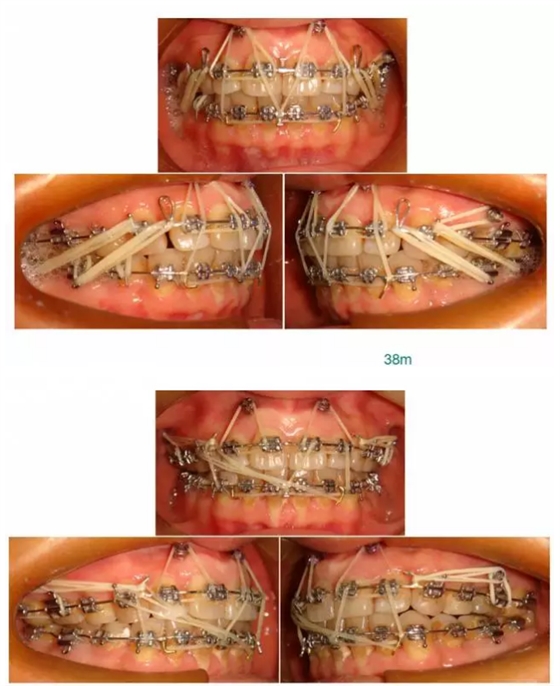

【原創(chuàng)博客】這樣的代償矯治大家滿意嗎?(重度骨性二類)——侯志明